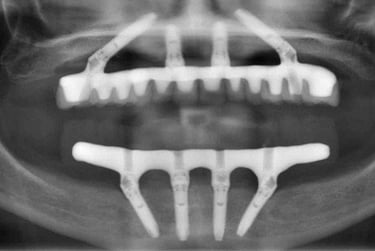

W dniu zabiegu pacjentowi wszczepia się 4 implanty w odpowiednio dobranych miejscach w szczęce i/lub żuchwie. Na implantach już w dniu wykonania zabiegu mocuje się stały most z pełnym uzębieniem w linii uśmiechu. Po pół roku pierwszy (tzw. tymczasowy most) wymieniany jest na most stały wzmocniony specjalną tytanową belką (oczywiście niewidoczną i niewyczuwalną).

Zdjęcia dzięki uprzejmości prof. Paulo Maló. Prezentacja na forum korporacyjnym sponsorowanym przez Nobel Biocare na dorocznym kongresie Europejskiego Stowarzyszenia na rzecz Osseointegracji, Lizbona, 27 września 2019 r.

Chirurg umieszcza 4 tytanowe implanty w kości szczęki i/lub żuchwy w punktach zaplanowanych wcześniej na podstawie tomografii pacjenta.

Tymczasowy most jest przykręcony na stałe już w dniu zabiegu chirurgicznego. Most jest w pełni funkcjonalny i bardzo estetyczny.

Do implantów mocuje się specjalne łączniki, na których potem zamontuje się stały most.